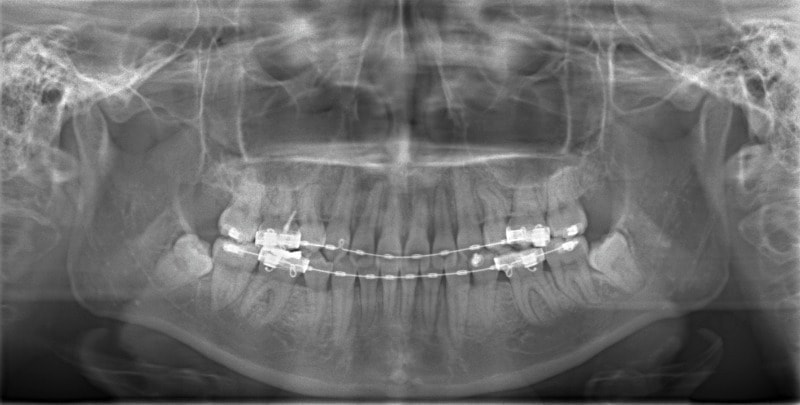

検査時パノラマレントゲン

特に小臼歯部に叢生があり、8番(親知らず)も埋伏しています。8番と7番の接触部分に吸収が若干あるような所見が認められます。